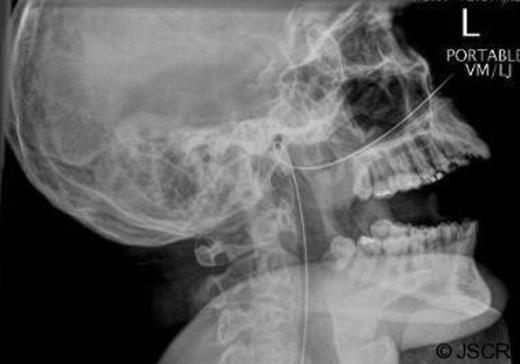

After passing the guidewire into the proximal jejunum without any problems and withdrawing the scope, an attempt was made to pass the plastic feeding tube over the guidewire. The tube would not advance past the naso-pharynx despite lubrication and gentle pressure. An attempt was made to advance the guidewire further but resistance was encountered. On attempting to withdraw the wire resistance was again encountered, and the patient reported severe discomfort on swallowing, which persisted (Figure 1).

Plain radiograph of the head and neck was performed, showing an alpha-loop having formed in the naso-pharynx